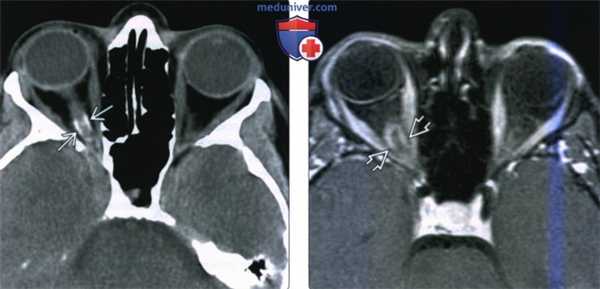

(Слева) КТ с контрастированием, аксиальный срез: у беременной женщины 26 лет с внезапной потерей зрения определяется накапливающее контраст супраселлярное объемное образование.

(Справа) Исходя из опасения о наличии геморрагического новообразования гипофиза была проведена МРТ. На корональных Т2-ВИ определяются нормальный гипофиз в сочетании с расположенным над ним гиперинтенсивным объемным образованием ( четкими контурами, которое развивается из диафрагмы седла. Отчетливо наблюдается отсутствие связи образования с железой. При хирургическом лечении была диагностирована классическая менингиома диафрагмы седла (grade I). (Слева) КТ с контрастированием, аксиальный срез: у пациента с первичной менингиомой оболочки зрительного нерва отмечается интенсивное контрастирование левого зрительного нерва. Данные изменения описаны в литературе как симптом «трамвайной линии».

(Справа) МРТ, постконтрастное Т1-ВИ, аксиальный срез: у другого пациента с вторичной менингиомой оболочки зрительного нерва определяется менингиома, растущая из области клиновидного гребня вокруг переднего наклоненного отростка, сужающая пещеристый сегмент внутренней сонной артерии, распространяющаяся через зрительный канал и инфильтрирующая оболочку зрительного нерва.